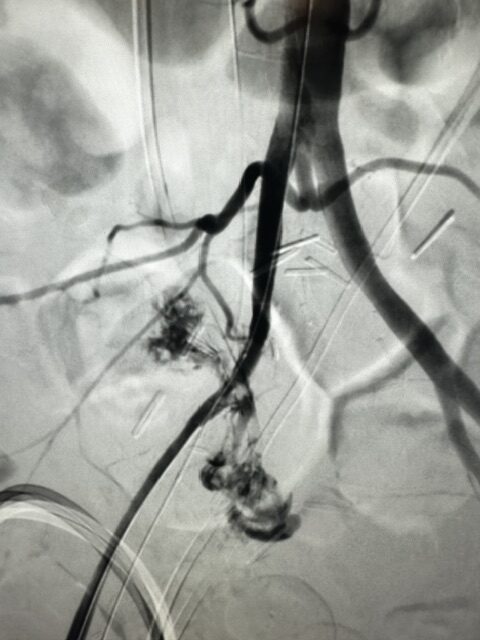

| How it works | Particles block blood supply to fibroids through a 2mm puncture; fibroids shrink over months | Uterus surgically removed through abdominal, vaginal, or laparoscopic approach |